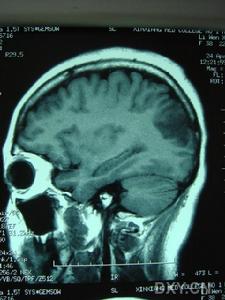

影像學上有類似Binswanger病的表現,MRI顯示在腦室周圍白質、腦幹、小腦中腳、基底節區和丘腦部位多發性小的線狀、點狀病灶,可在皮質下對稱融合成片狀。CADASIL臨床確診標準:在可能CADASIL診斷標準的同時,與第19號常染色體連鎖和(或)病理證實有顆粒狀嗜鋨性物質沉積改變的小動脈病。可能為CADASIL的診斷標準:①50歲前發病;②出現下列臨床表現中至少2條:症狀持久的腦卒中發作、偏頭痛、明顯的情感異常、皮質下痴呆;③無腦血管病的危險因素;④常染色體顯性遺傳證據;⑤MRI顯示腦白質異常,而無腦皮質梗死灶。

⑥影像學檢查:MRI顯示非典型性腦白質病。可見,腦室周圍多發的梗死灶及白質變性,可累及兩側半球皮層、白質及腦室周圍、基底節、橋腦白質等部位。

影像學檢查示:患者姐弟的CT均可見,但當地的CT顯示欠清楚。患者的頭顱CT可見多發白質變性;MRI清晰可見多發白質變性及小梗死病灶,病灶大小不一,均呈長T1、長T2信號,病灶累及雙側半球、腦室周圍、腦幹、橋腦,小腦未見病灶;梗死灶分布在底節區,MRA(血管的磁共振影像)顯示顱內血管正常。